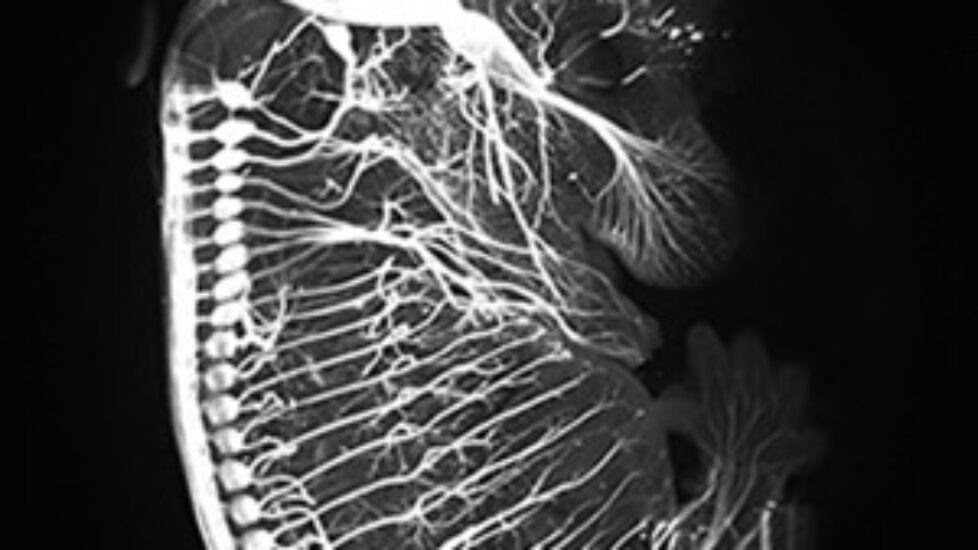

Imaging breakthrough. Images generated using the new iDISCO technique show nerves responsible for conducting pain and other sensations, in a mouse embryo (top); axons of the motor nerve that that controls eye movements, in an adult mouse (middle); and collecting ducts that concentrate urine before it leaves the kidney, in an adult mouse (bottom).

Newswise — In a significant technical advance, a team of neuroscientists at The Rockefeller University has devised a fast, inexpensive imaging method for probing the molecular intricacies of large biological samples in three dimensions, an achievement that could have far reaching implications in a wide array of basic biological investigations.

The new method, called iDISCO, optimizes techniques for deep tissue immunolabeling and combines them with recent technological innovations in tissue clearing and light sheet microscopy to achieve unprecedented deep labeling and imaging of molecular structures in the brain, the kidney, and other organs and tissues in experimental settings. A detailed report on iDISCO is in the November 6 issue of the journal Cell.

“For us as neuroscientists, one of the big applications of this new imaging method has been the ability to visualize axonal pathways in the developing and adult brain,” says Nicolas Renier, a postdoctoral associate in the Tessier-Lavigne laboratory and co-first author on the study. “We were surprised at just how well we were able to image these detailed structures in the context of the whole brain.”

“The fact that we can now visualize neural circuit formation in larger embryos allows us to study the developing nervous system when it is more well formed,” says Zhuhao Wu, also a postdoctoral associate in the Tessier-Lavigne laboratory and co-first author on the study. “This opens entire new avenues to our research.”